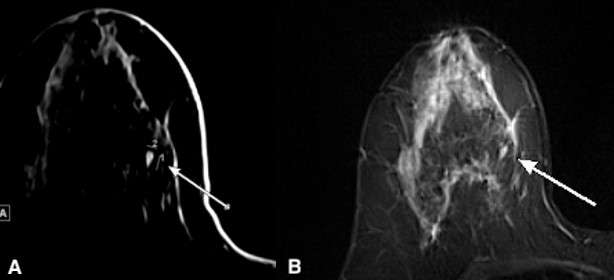

Figure 3. MRI of the breasts with STIR (A) and fat-saturated T1 post contrast (B) sequences showing a 7 x 4 mm circumscribed oval mass with STIR hyperintensity (A) and homogenous enhancement (B). Though subtle, fat-saturated T1 post contrast images show dark internal septations. These findings are suggestive of fibroadenoma.